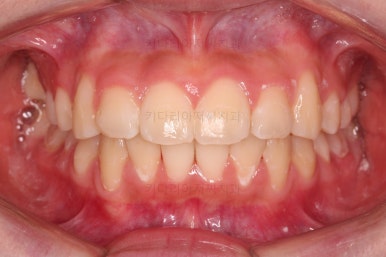

치료 마무리 사진입니다.

연산동치과 전후사진을 비교해 볼게요.

치열이 가지런해지고 교합도 좋아지고 웃는 모습도 매우 좋아졌네요.

비발치 덧니교정이었지만 입이 튀어나오거나 하지 않고 오히려 치아 각도나 입매가 약간 디ㅜ로 들어가면서 입매도 자연스러워졌어요.

충치치아도 깨끗한 치료가 되었고요.